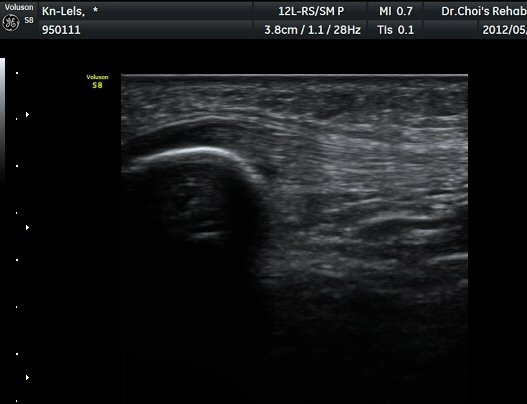

½½°³°ñ¾Æ·¡ ÈûÁÙ Á¾´Ü¸é°Ë»ç¿Í Ⱦ´Ü¸é°Ë»ç¿¡¼­ ÈûÁÙÀÇ ºñÈİ¡ °üÂûµÇ°í(±×¸² 3, 4).